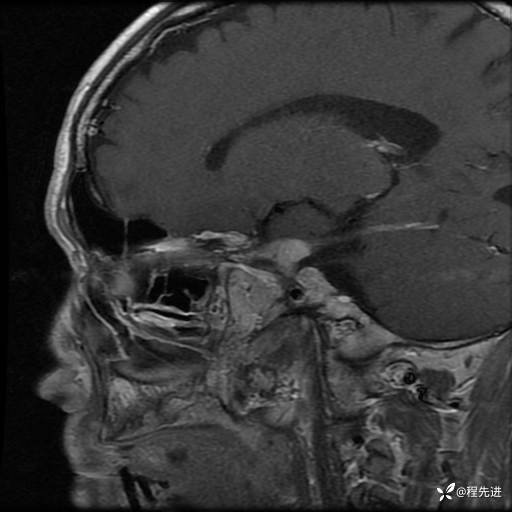

【神经】特别精彩病例|老年人,出现视物重影2月余,鞍区占位期待您的精彩解读!

患者性别:男

患者年龄:74岁

简要病史:出现视物重影2月余,未予重视,2月来症状逐渐加重

MRI平扫+增强:

T1增强: